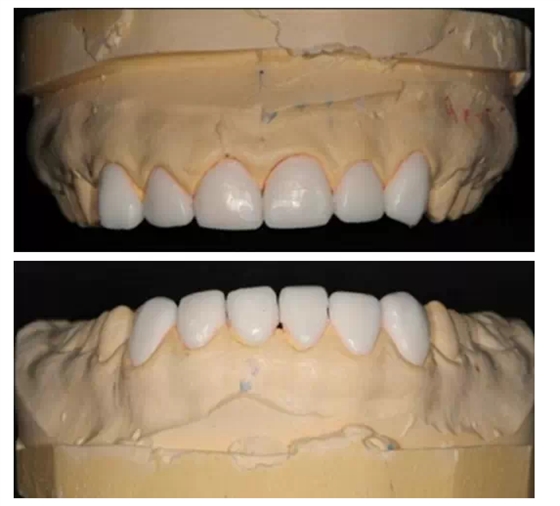

這時(shí)醫(yī)生已經(jīng)拿到技師做好的美學(xué)蠟型,可以讓患者看到與之前最直觀的對(duì)比。

如同買房子,美學(xué)蠟型當(dāng)于沙盤,沙盤可以制作的無(wú)比精良,但是僅僅看到沙盤是不夠的,我們必須要看到樣板間,準(zhǔn)確的知道這套房子最終會(huì)建成什么樣子,這就是我經(jīng)常和大家提到的Mock up(樹脂罩面)。

把技師做好的美學(xué)蠟型,用臨時(shí)冠材料準(zhǔn)確的復(fù)制到患者的口內(nèi),讓患者最直接的看到修復(fù)后的效果。如果需要進(jìn)行少量的牙體預(yù)備,一定要征求患者同意后再進(jìn)行。